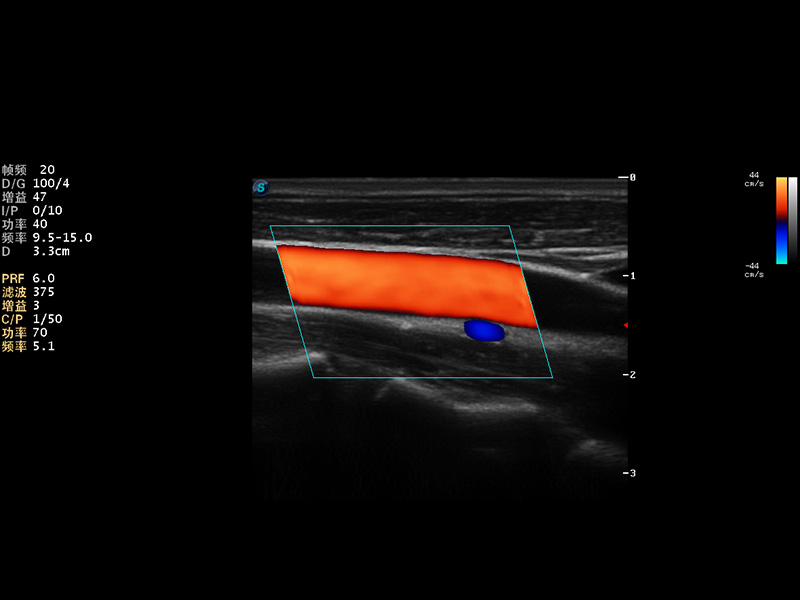

S9便携式彩色多普勒超声诊断仪是db真人体育官网研发的高端便携彩超设备,外观设计新颖、产品性能卓越。S9在便携超声领域采用了突破传统的触摸屏交互设计,并以先进的软件硬件技术和设计理念,为您带来清晰的图像质量、稳定的工作性能和便捷的操作体验。

AutoC智能血流追踪